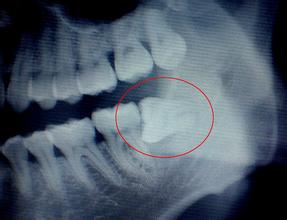

智齒要拔嗎?有些人認(rèn)為是智齒是一種智慧的象征不能拔除,但是漳州衛(wèi)生職業(yè)學(xué)院附屬口腔醫(yī)院醫(yī)生表示:生長(zhǎng)不得當(dāng)?shù)闹驱X會(huì)影響口腔健康,所以不要認(rèn)為智慧牙是不可拔出的,那樣生長(zhǎng)不健康的智齒是一種危害對(duì)口腔來說。

首先,那些阻生智齒,也就是智齒所處位置不利,被埋在牙床骨中無(wú)法順利長(zhǎng)出,并引發(fā)牙齦腫痛、發(fā)炎等癥狀的,最好拔掉。否則,炎癥可能會(huì)危害全身健康。如果智齒和其他牙齒擠在一起,也應(yīng)該拔掉。此外,如果患者嘴巴較小,最好也考慮拔掉智齒。因?yàn)樽彀托〉娜耍⒀罆r(shí)牙刷很難達(dá)到智齒部位,用牙簽或牙線清潔也不容易,經(jīng)常會(huì)引發(fā)感染、蛀牙等問題,并危及整個(gè)口腔。